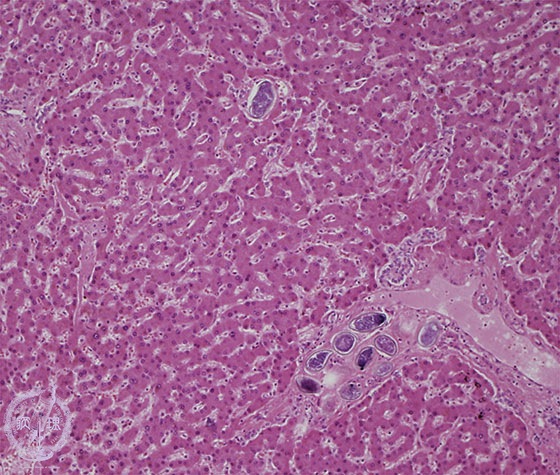

- (6)Schistosomiasis japonica

Microscopic image (HE stain, intermediate power) Parasite eggs are found in the portal and central veins. Fibrosis is inconspicuous.